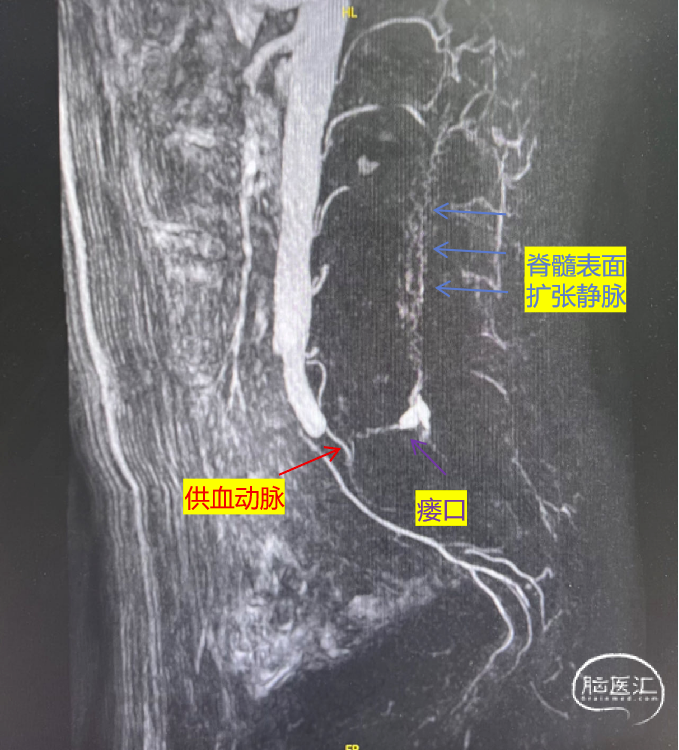

图3.我院腰骶部MRA示瘘口位于L5水平

穿刺左侧桡动脉,使用4F 125cm ver导管分别超选双侧髂内外动脉以及腰5、骶正中动脉,发现SEDAVF由双侧髂内动脉分支及骶正中动脉供血,可见扩张的瘘口静脉端,瘘口位于腰5水平。

局麻后穿刺左侧股动脉,置5F动脉鞘,泥鳅导丝配合4F SIM2导管腹主动脉成袢后,超选至左侧髂内动脉,使用微导丝、微导管超选至供血动脉,微导管内造影可见瘘口静脉端呈瘤样扩张,引流至椎旁静脉丛以及向硬膜下脊髓静脉逆流,SEDAVF诊断明确。

本例患者由于主动脉分叉解剖成角,以及分支发出部位不利于导管稳定,所以传统经股脊髓血管造影不具优势,反而经桡可以顺利超选,明确多根供血动脉。本例患者经桡造影发现双侧髂内动脉分支及骶正中动脉均参与供血。挑选供血较明显的左侧髂内动脉分支进行微导管超选造影,可见瘘口静脉端呈瘤样扩张,引流至椎旁静脉丛以及向硬膜下脊髓静脉逆流,最终明确诊断为SEDAVF。